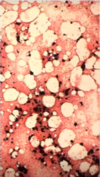

Megakaryocyte

* platelet series

* multiple condensed nuclei

* large size

* not counted in M:E ratio